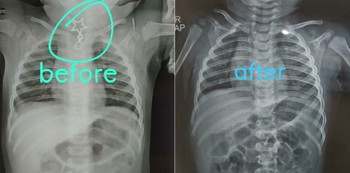

After the baby swallowed the pendant, his parents rushed him to Dr Rastogi’s OPD. An X-ray was conducted and the sharp-edged pendant was seen lodged in the child’s neck area (image above).

The doctor then started an endoscopy procedure to take the locket out. But the greatest challenge for the doctor was to remove the locket without any internal injury.